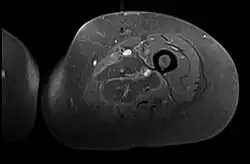

Axial fat suppressed post gadolinium contrast enhancement MRI image showing absent enhancement in the left thigh adductor muscles centrally indicating necrosis in diabetic myonecrosis.